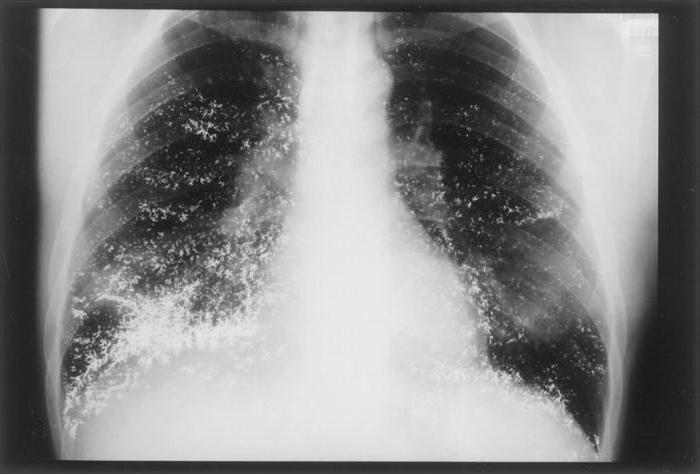

Фотографии бактерий, вызывающих бактериальные пневмонии у животных

Раздел: Другие животные